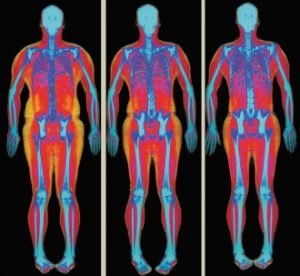

Pierderea în greutate (25)

Metabolism (10)